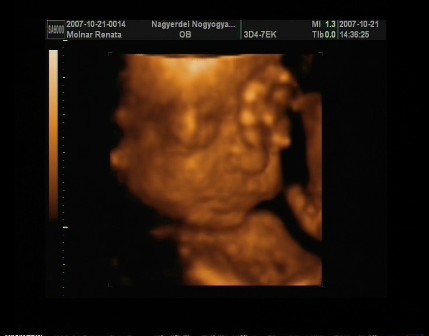

No jöttem beszámolni a pénteki UH-ról. A 4D-s UH végül 2D-s lett,mert a baba fekvése miatt semmi értelme nem lett volna a 4D-s UH-nak.Ugyanis a lelkem harántfekvésben van változatlanul,és a 15perces vizsgálat alatt végig háttal volt nekünk. Pedig nagyon meg lett macerálva és az istennek se akart megfordulni.Doki kb.5percig fel alá járkáltatott hátha felélénkül a drága,de nem...Kellett a bal oldalamra,és a jobb oldalamra is feküdnöm,ám ez sem segített. Finoman ütögette az érzékelőfejjel a hasamat és erre se akart megfordulni.Kis dacos... Ebéd után voltunk UH-on,doki kérdezte is hogy nem-e most ettem,mert baromi higgadt,nyugodt volt a baba,nem nagyon mozgott,és ugyebár meg se fordult.Erre mondtam,hogy igen...kiderült,hogy lehet hogy jobb lett volna ha éhgyomorra megyek,mert akkor élénkebb lett volna.Azt mondta a doki,hogy biztos most ő is jól van lakva,és pihen. A sok macerálás hatására azért háttal nekünk,de elkezdte a kezét,és a lábát emelgetni,meg picit a fejét is.Szegénykémet picit sajnálom,mert nagyon szűk még neki odabent ahogy elnéztem... Ő baromi gyorsan fejlődik,a vizsgálat napján én elvileg 15hetes1napos voltam,de a fejlettségi szintjét nézve a drágám,már akkor 15hetes5naposnak felelt meg. Látszik is,mert baromi pici helyen,teljesen kitölti az egész méhemet!Úgyhogy szerintem hamarosan nagyot fogok pocakosodni...

A csodálatos értékei: a 2 fejkörfogat-->HC: 11.36, BPD: 3.34, pocikörfogata: 9.64(jó nagy már most... ), mellkas körfogata: 2.87, combcsontja: 1.70.